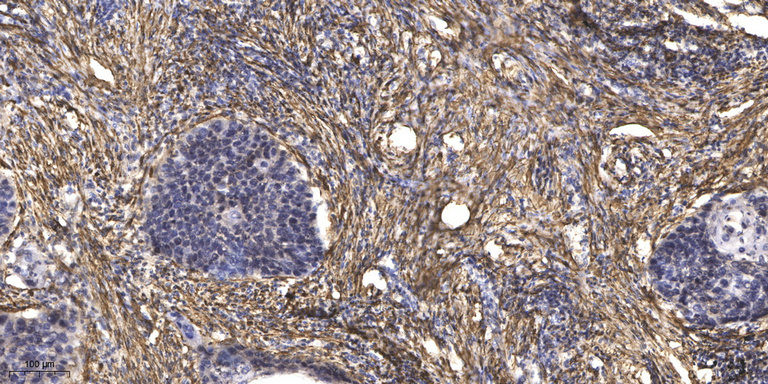

WB, IHC, IF, IP

Optimal working dilutions should be determined experimentally by the investigator; Suggested starting dilutions are as follows:IHC 1:50-300; IF 1:200.

α-tubulin Monoclonal Antibody(8F11) AbFluor™ 680 Conjugated specially designed for your Immunofluorescence analysis.

α-tubulin Monoclonal Antibody(8F11) AbFluor™ 680 Conjugated specially designed for your Immunofluorescence analysis.

Cellular Localization:

Cytoplasm, cytoskeleton.